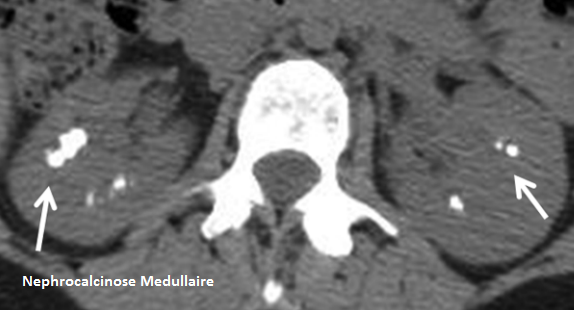

- Calcifications de la médullaire → Finit en Néphrocalcinose médullaire